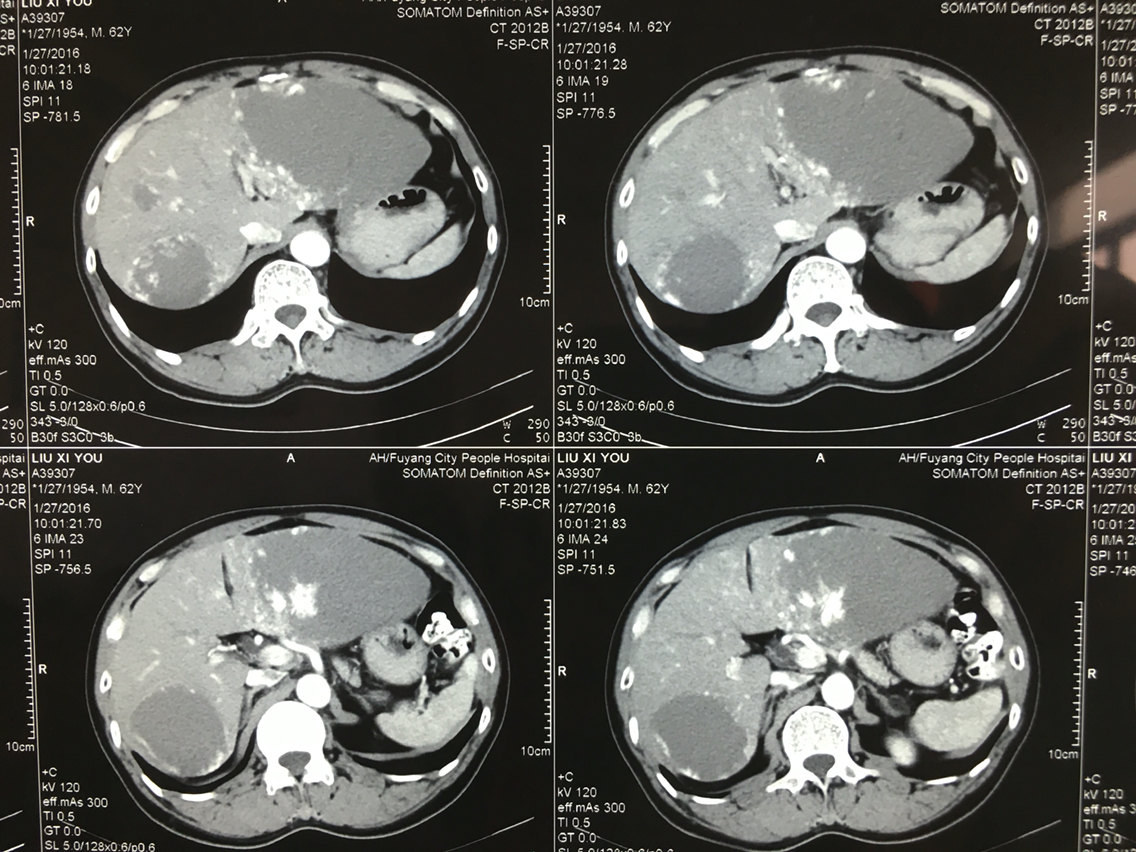

由于肝血管瘤生长缓慢,大多数无临床表现,直径较小的肝血管瘤一般不需要治疗。 建议每3-6个月复查彩色超声或腹部CT以监测变化。